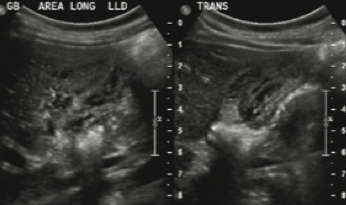

Anshu Kumari, MD; Magda Mendez, MD, FAAP; Sandra Camacho, MD; Amir Navaei, MD

Echogenic bowel has been defined as bowel of similar or greater echogenicity on ultrasonography than surrounding tissues, such as liver, bones, and lung.